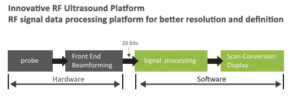

Unique RF Platform

Because of hardware limitations, traditional front-end RF platforms are unable to transmit certain useful information. VINNO’s unique platform is the first in the fast processing power to ensure detailed images and accurate measurements. The RF platform reads a wider range of signals, resulting in clearer, higher-resolution images. This endows the system with unique capabilities, including full screen mode and high-resolution images free of distortion, which aids in diagnosis of small lesions